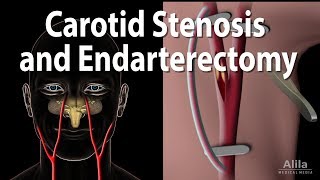

Flow visualization of a carotid artery bifurcation Carotid Stenosis and Carotid Endarterectomy, Animation

Flow visualization of a carotid artery bifurcation Carotid Stenosis and Carotid Endarterectomy, Animation

Carotid Stenosis and Carotid Endarterectomy, Animation CAROTID ULTRASOUND: THE CAROTID BIFURCATION